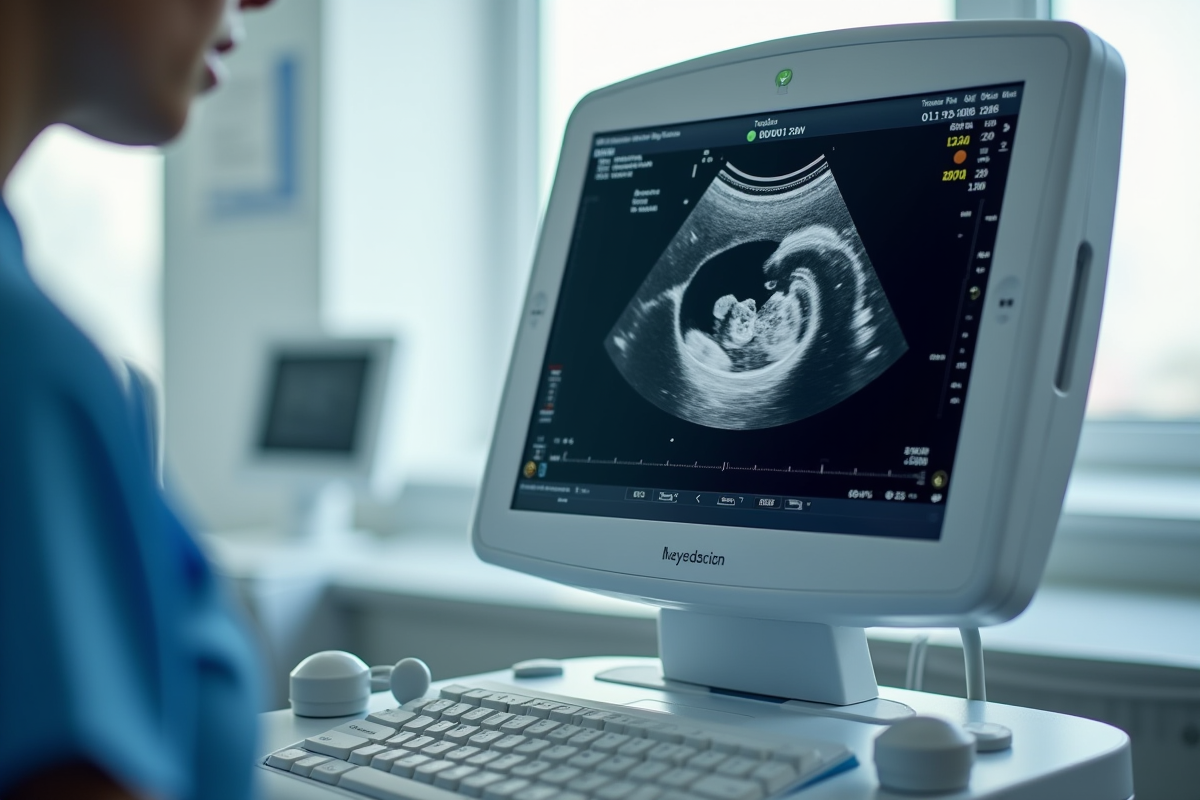

Échographie

L’échographie est l’un des outils les plus couramment utilisés. Elle permet de visualiser le fœtus et d’évaluer son développement. Ce test non invasif, réalisé à plusieurs moments clés de la grossesse, détecte les anomalies structurelles et mesure la croissance du bébé.